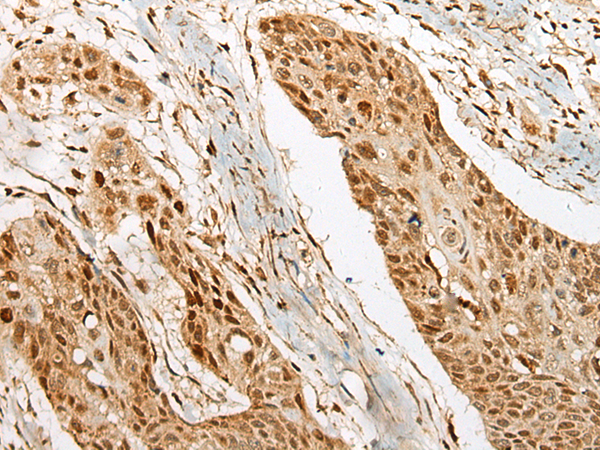

IHC (Immunohistochemistry)

(Immunohistochemistry of paraffin-embedded Human esophagus cancer tissue using UBTF Polyclonal Antibody at dilution of 1:25(×200))